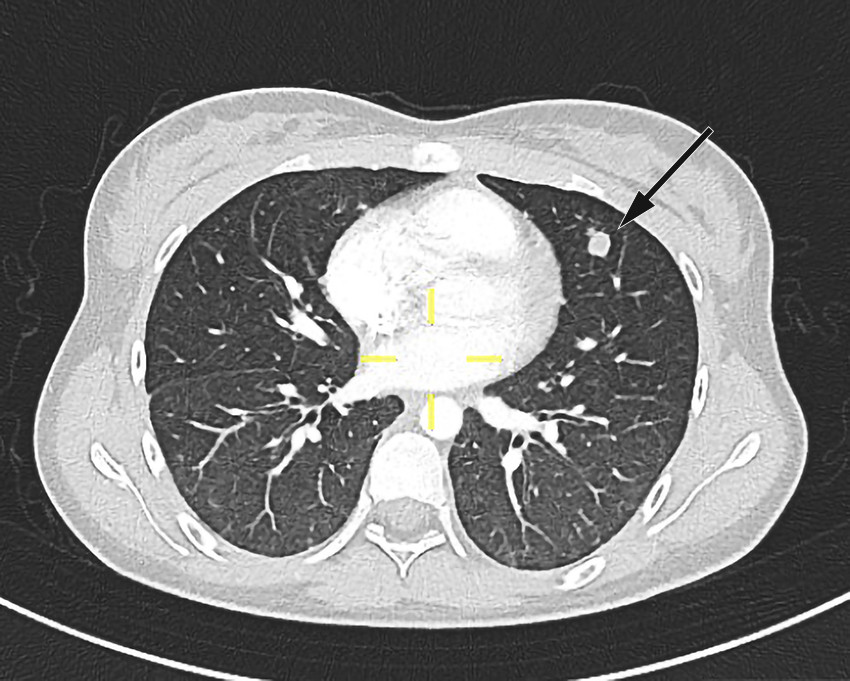

Pasienten ble videre undersøkt av vakthavende øre-nese-hals-lege. Man mistenkte abscedering, men trismus og smerter gjorde at det var vanskelig å få gjennomført en fullgod halsundersøkelse. Det ble derfor rekvirert CT collum. CT-funnene var forenlig med tonsillær/peritonsillær abscess bilateralt samt høyresidig trombosert vena jugularis med ledsagende tromboflebitt og flegmonøs betennelse (figur 1). På bakgrunn av dette ble Lemierres syndrom mistenkt. Abscessene ble vurdert som ikke modne for drenering, og det ble anbefalt bytte av antibiotika til klindamycin intravenøst, 600 mg × 3, hvilket ble startet opp neste dag. Grunnet trombosetendensen ble det også forordnet lavmolekylært heparin (enoksaparin), dosering 60 mg subkutant morgen og 40 mg subkutant kveld. P-piller (etinyløstradiol) ble seponert, da disse kan gi økt trombosetendens.

Pasienten fikk smerter i venstre del av toraks på dag 2. CT toraks og abdomen viste funn forenlig med septiske embolier i begge lunger og mulig infarktkomponent i høyre underlapp (figur 2, figur 3). I tillegg var det lett forstørret lever og milt, periportalt ødem samt små mengder fri væske i bekkenet (mulig fysiologisk). Det var også beskrevet mistanke om tromber i vena subclavia og vena axillaris på høyre side. Dag 3 så man oppvekst av penicillinfølsomme Streptococcus anginosus i blodkultur. Serologiske prøver viste svakt positivt Epstein-Barr-virus (EBV)-viralt kapsidantigen (VCA)-IgG, svakt positivt EBV-VCA-IgM og negativt EBV-EBNA-IgG. Intravenøst benzylpenicillin og klindamycin samt antikoagulasjonsbehandling med lavmolekylært heparin (enoksaparin) ble kontinuert.